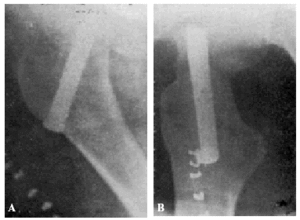

Fracaso número 2(observación número 2). F. S., setenta años4. Ingresa en el servicio con una fractura mediana del cuello femoral izquierdo. Osteosíntesis extraarticular (fig. 3. A y B). La impactación no ha resultado perfecta.

Figura 3. A: obs. núm. 2. El clavo no penetra suficientemente y la impactación, salvo en la parte superior de la línea de fractura, es muy defectuosa. B: obs. núm. 2. La posición del clavo es buena. C: obs. núm. 2. El clavo tiende a ser expulsado hacia fuera y apenas penetra en la cabeza femoral.

A los veinte días de la intervención pasa el enfermo a su domicilio, recomendándole que continúe en la cama. Pasado un mes vemos nuevamente al enfermo, el cual nos manifiesta que anda con mucha más dificultad que en los primeros días de permanecer en su domicilio, que fue cuando, por no haber interpretado bien nuestras indicaciones, comenzó a emprender la marcha. La radiografía (fig. 3. C) demuestra que el clavo apenas penetra en la cabeza femoral. A los ocho días hacemos otra radiografía (fig. 4. A), observándose que el trocáncer ha ascendido, a pesar de continuar guardando cama el enfermo. Ingresa nuevamente en el servicio, donde, con anestesia raquídea, retiramos el clavo, reduciendo las fracturas y volviendo a colocar un clavo más largo en buena dirección (fig. 4. B). Una radiografía practicada siete años y medio más tarde demuestra la no consolidación de la fractura, trastornos tróficos en cuello y cabeza femoral y que el cabo ha penetrado en el fondo de la cavidad cotiloidea, en donde ha labrado una cavidad (fig. 4. C).

Figura 4. A: obs. núm. 2. El trocánter ha ascendido francamente con relación a la radiografía anterior. El clavo tiende a salir de la cabeza por su parte superior. B: obs. núm. 2. Se extrajo el clavo y se colocó otro. El nuevo clavo está colocado en buena dirección, pero la reducción no es perfecta. C: obs. núm. 2. El clavo ha penetrado en el fondo de la cavidad cotiloidea, en cuyo lugar ha labrado una cavidad. Trastornos tróficos en cuello ycabeza femoral. El cuello del fémur ha desaparecido casi completamente.

En este caso el fracaso se debe a que la impactación no fue perfecta, y sobre todo, a haber el enfermo iniciado la deambulación al mes de intervenido, a pesar de que nosotros le ordenamos que guardara cama.